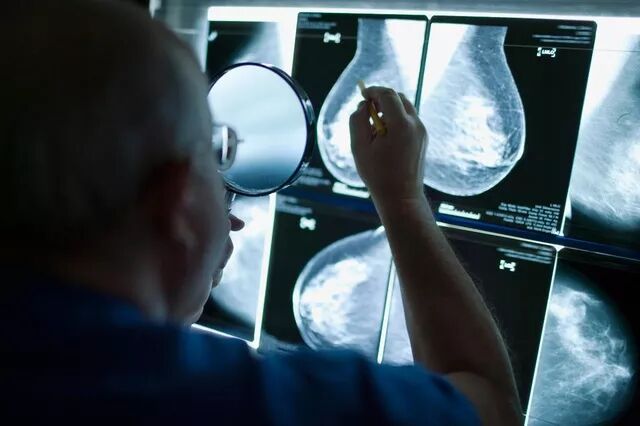

左手拿探头,右手拿“穿刺枪”, 范照青做穿刺时的劲儿与他的微信头像一样,颇有李连杰的范儿,只不过他穿着手术服戴着口罩。范照青是北肿乳腺预防治疗中心的副主任,科里都叫他大范。

范照青手里的 “枪”带有一支空心针,他要在超声探头的引导下,在乳房上准确找到目标,把长针刺进去,扣动扳机,“咔”的一声后抽出针管,护士张(吉吉)用镊子从针管里取出一条1厘米左右的条状组织,泡在福尔马林的标本瓶。如此取三条,送去病理科做检查。

左手探头右手枪,是欧阳涛培养的医生做穿刺时的基本行头,也是科里所有主治医师都必须掌握的技能。

中心主任欧阳涛如此行事的原因,依然是为了效率。一般情况下,这项工作是由超声科大夫和外科大夫一起配合完成,而在这里,任何一位经过培训的主治医师都可以在护士的协助下独立完成这项操作。2004年至今,已经完成了16000多例,近几年来,他们乳腺中心每年做的超声影像引导穿刺比医院超声科完成的还多。